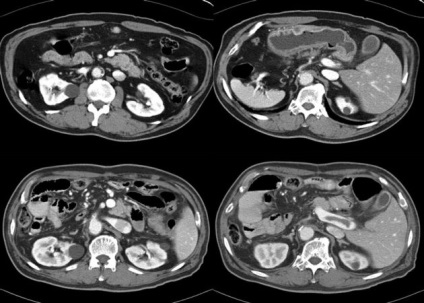

IRM (imagistica prin rezonanta magnetica) - un tip de scanare a corpului, în care pentru obținerea de imagini detaliate aplicate câmpuri magnetice si unde radio puternice. Studiul a fost realizat cu ajutorul scanner RMN.

RMN a abdomenului se face la:

- determinarea perfuzia organelor abdominale;

- determina cauza dureri abdominale;

- examinarea ganglionilor limfatici ale abdomenului;

- diagnosticarea diferitelor boli ale ficatului, rinichilor, pancreasului sau splina.

RMN-ul poate distinge tumorile de la tesuturile normale, ceea ce ajuta medicii pentru a determina mărimea și distribuția acestora.

Avantajul IRM a abdomenului este nedureros si confortabil pentru pacient, nu este nevoie de anestezie, o examinare a intestinului subțire și a diagnostica alte organe abdominale.

Pentru inspectarea unei intestinului subțire sau de mare este necesar să se utilizeze tehnici speciale care utilizează IRM opacifiere. Fara acest RMN conventionale are o valoare de diagnostic ridicată.

Studiul este de dorit să continue puternice și moderne mașini IRM care scanează corpul foarte repede. În cazul în care procedura durează prea mult, valoarea sa de diagnosticare este scăzută, la fel ca în calitatea imaginii afectează puternic peristaltismul intestinal.

scanner RMN - o țeavă mare, care conține magneți puternici. O persoană care în timpul inspecției este în interiorul acestui tub. RMN-ul poate fi utilizat pentru a examina orice parte a corpului uman, inclusiv intestine.